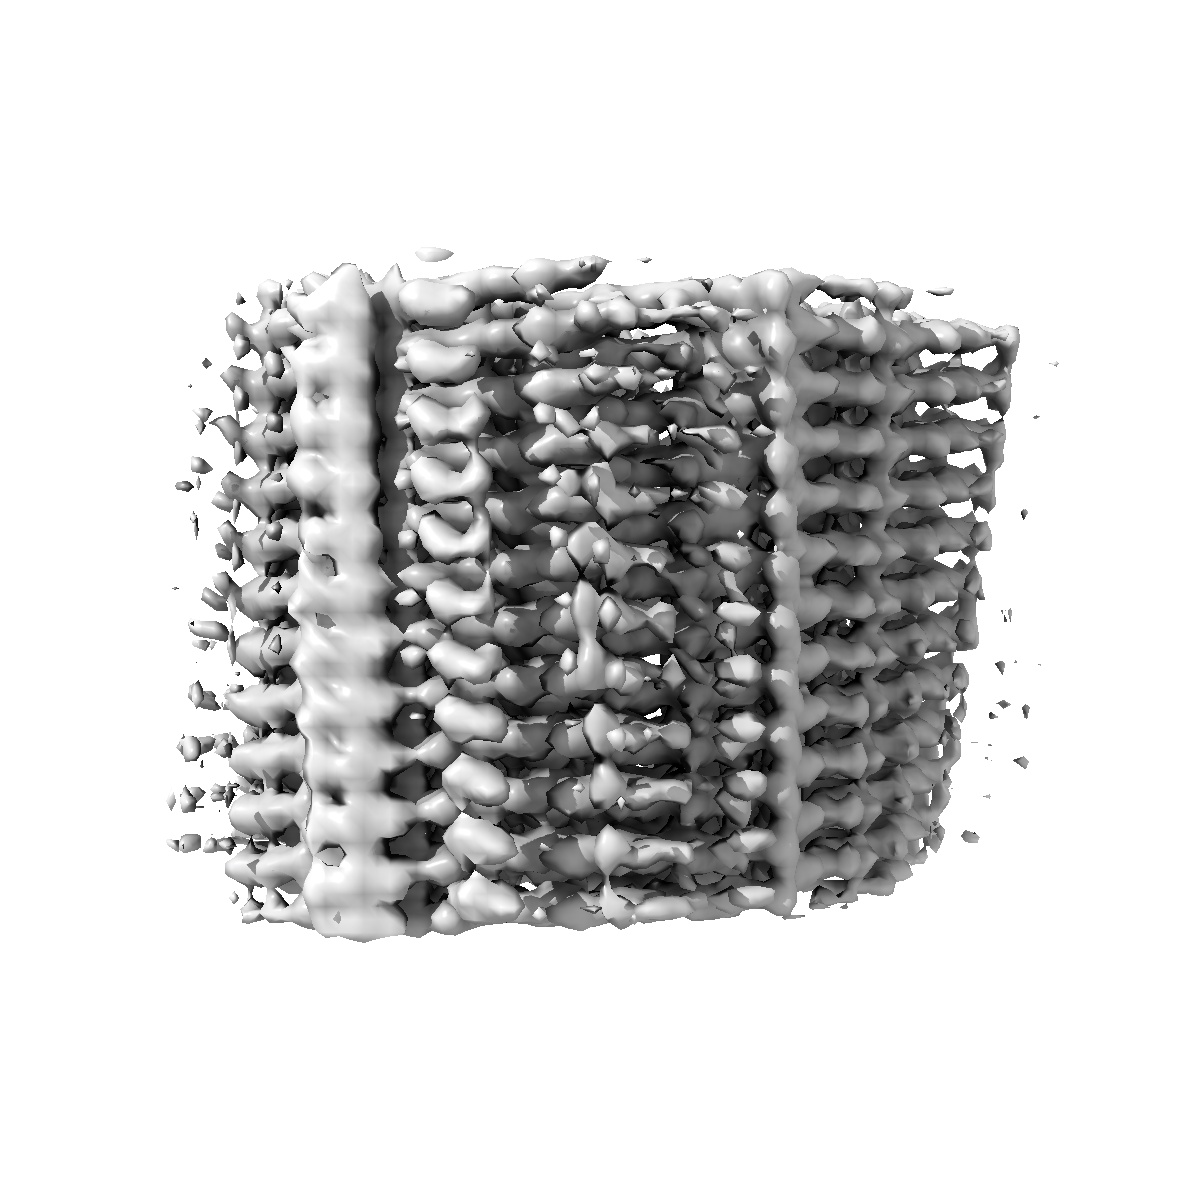

Cryo-EM structure of amyloid fibril extracted from heart of a variant ATTR T60A amyloidosis patient 1

Helical reconstruction3.4 Å

Sample: Cardiac amyloid fibril of a variant ATTR T60A amyloidosis patient

Structural and molecular homogeneity of ATTRv-T60A amyloid fibrils across patients and organs.

(2025) Structure , 33 , 2013 - 2019.e4